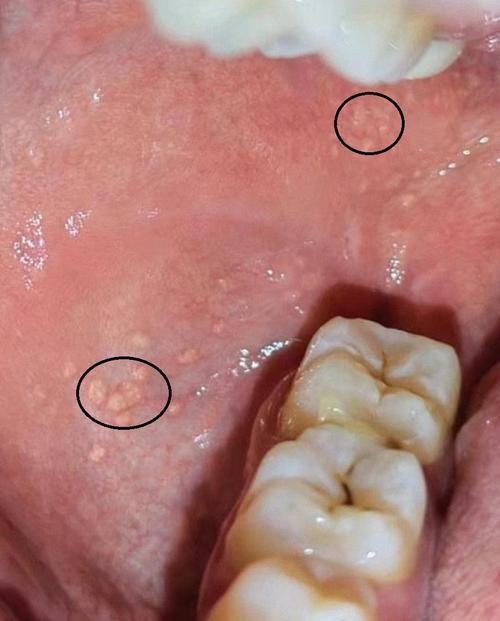

典型的临床表现:黄色或黄白色小丘疹/小斑点

这是迷脂症最核心、最典型的症状,您会在口腔黏膜上看到一些微小的、针尖至米粒大小的、黄色、淡黄色或黄白色的扁平或略微凸起的小丘疹或斑点。

- 颜色:颜色通常比周围的黏膜要浅,有时会被误认为是食物残渣或脓疱。

- 形状:多为圆形或椭圆形,表面光滑,质地柔软,用手触摸时没有痛感或异常感觉。

- 数量:数量可多可少,从几个到几十个甚至上百个都有可能。

- 颊黏膜:这是最常见的部位,尤其是在口角内侧、上下咬合线对应的颊黏膜区域。